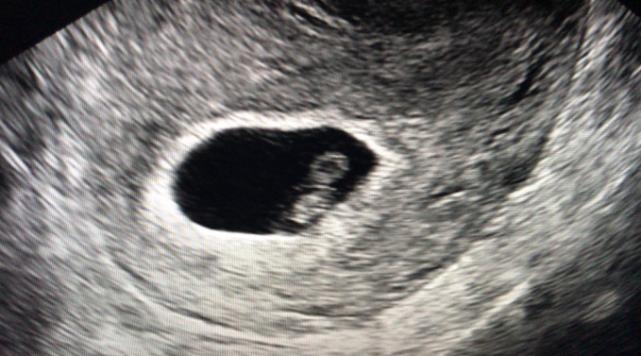

据介绍,今年6月,郑女士夫妇顺利进入了IVF治疗周期,经历了一系列降调节、促排卵、体外受精、胚胎培养等过程,最终在7月14日,选择移植了两枚胚胎,术后给予精准保胎治疗,移植15天后检查HCG结果显示郑女士怀孕了,移植后28天B超检查一切正常,这一好消息令患者及所有医护人员均兴奋不已,祝福郑女士夫妇终圆好“孕”之梦。